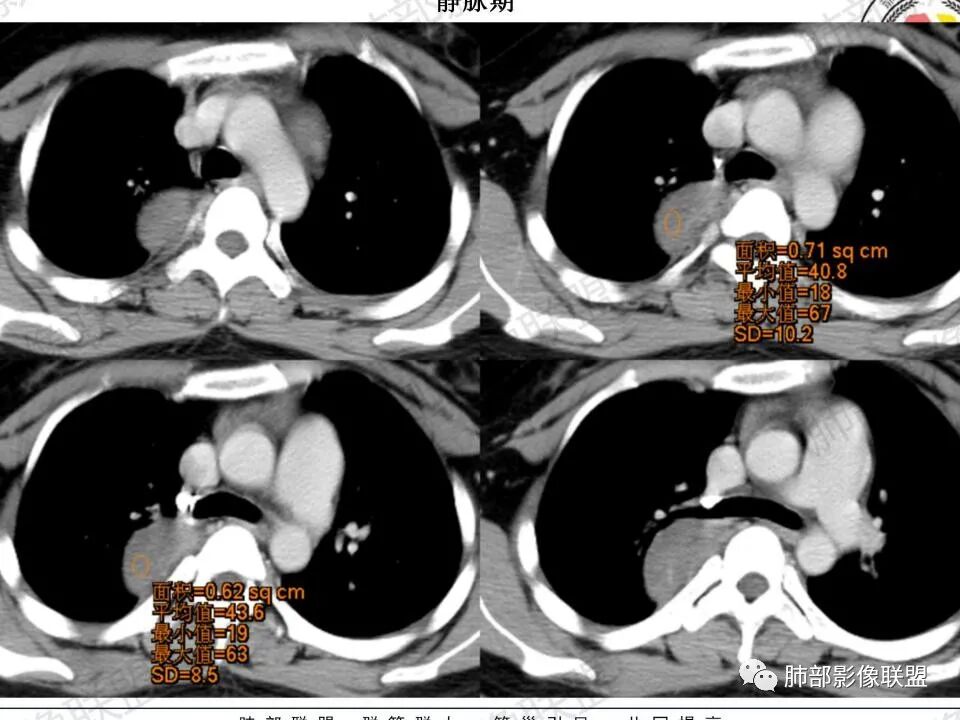

CT值平扫33HU,增强:45HU左右

定在轻度强化

(3)增強:

后纵隔神经节细胞瘤常动脉期无明显強化、或轻度间隔、包膜或瘤体强化,延迟期可进一步斑片、结节状轻度或中度强化,强化程度进行增加,呈渐进性延迟强化,但強化程度一般为轻度到中度强化,究其原因可能是神经节细胞瘤瘤体内含有大量黏液基质和胶原纤维,使得细胞外间隙扩大,阻碍了对比剂的灌注,从而延缓了对比剂的积累,因此其动脉期多无明显强化或仅有轻度强化,延迟期呈渐进性轻度强化是后纵隔神经节细胞瘤强化特征。大部分病灶有轻度-中度强化,部分病灶无强化,这还可能与瘤组织内部间质血管含量多少相关,无强化病例瘤组织内部主要由胶质纤维和节细胞组成,间质血管较少,因此强化较低,而强化程度较高的病理可见较多的扩张、充血的毛细血管,引起较多的对比剂积蓄,因此强化相对明显。因此,神经节细胞瘤极少出现瘤组织早期强化,而多呈延长渐进性强化,增强扫描神经节细胞瘤内细胞成分可增强,黏液基质不强化。